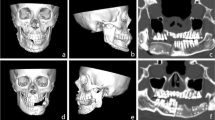

The DICOM files of each examination were imported into ProPlan CMF version 3.0.1 (Materialise, Leuven, Belgium). In this software, the DICOM images were segmented and converted into three-dimensional (3D) models of the pelvis. Therefore, the spine was cut above the Os sacrum and the femur was removed from the pelvis model. After segmentation, the model was saved as a standard tessellation language (STL) file.

Definition of a generalizable topology

As all geometrical models stored in STL files are arbitrarily meshed, a direct geometrical relation that allows statistical evaluation is not possible. Hence, it was necessary to define a mesh topology that can be individualized to represent the different geometrical shapes of the bones. To avoid geometrical errors due to mesh deformation, quadrilaterals were chosen over triangular meshes, as this allows a consistent topological flow, i.e., following anatomical features, such as the top of the iliac crest, and is more robust toward deformations (Fig. 1).

The topologies were designed to respect salient anatomical structures and to cover the portions of the iliac crest that are relevant for transplant harvesting in reconstructive surgery [15]. To individualize the standard topology in order to represent accurately the shape of each individual pelvic bone surface, a morphing based on guiding landmarks and a cascade of subsequent projection and mesh smoothing operations was performed as implemented in the software Blender version 2.7.8 (Blender Foundation, Amsterdam, Netherlands) and previously reported [16]

Alignment and averaging

Each of the 2000 pelvic models was imported into Blender version 2.7.8 (Blender Foundation, Amsterdam, Netherlands). First, a coarse alignment of the models was performed manually to place them in the center of the global coordinate system and give them matching orientations by turning and tilting until both iliac crests were at the same height and both spinae iliaca anterior superior were facing to the front. This coarse alignment was required to standardize the subsequent steps of generating topologically standardized meshes, as described in the previous section. By the use of a custom in-house developed plugin for the software Blender, anatomical landmarks were placed automatically in relation to salient geometrical features of the pelvic bone models. These landmarks were used to guide the geometry of the standardized topology. To allow for an individual fine adjustment, it was possible to modify the positions of these guiding landmarks. This step was performed by one single, specifically trained operator after defining standardized criteria. The geometrical data of the topologically standardized meshes was stored in a custom file format to allow subsequent statistical averaging.

In the scope of geometrical averaging, all data was loaded and aligned to a common coordinate system by applying the generalized Procrustes analysis (GPA) [17], while omitting scale correction. By doing so, averages were calculated for the whole population.

The cutting guides were designed on the 3D model of the averaged pelvis. One cutting guide was designed for each group and one cutting guide was designed on the 3D model of the pelvis, which was averaged from all models (UNIV: overall averaged cutting guide group). The guides were designed with hockey stick layout and an offset of 1 mm to the pelvis. The width of the cutting guides was 30 mm measured from the iliac crest to the caudal border and 30 mm from the spina iliaca anterior superior to the dorsal border (Fig. 2). This design was chosen because it represents the maximum bone portion nourished by the circumflex ilium profunda artery, which is the nourishing vessel. The vessel reaches the Spina iliaca anterior superior at the medial side of the iliac crest [18]. It continues dorsally on the inner side and gives off small branches to the bone. After about 6 cm it crosses the iliac crest, and from there it nourishes the bone [19]. The total length was 80 mm. Also, if bone elevation to the sacroiliac joint is possible, this length is sufficient for most mandibular reconstructions and keeps the integrity of the sacroiliac joint.

Evaluation of the models was performed in Geomagic Control X (3D Systems Corporation, Rock Hill, SC, USA). In the software, the thickness of the model was measured (Fig. 3). The mean thickness, and the maximum thickness as well as the volume of the space between the cutting guide and the model of the pelvis were recorded.